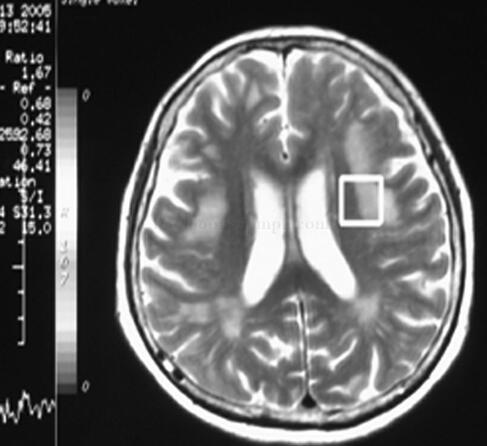

女75岁,反复肢体麻木无力16年和视力下降2月

1小时条评论女性,75岁,右利手。 主诉:反复肢体麻木无力16年,双眼视力相继下降2月。 病史:1989年10月初,患者右上臂外侧出现大片皮疹,伴右侧上肢针刺样疼痛,轻触如刀割。按带状疱疹治疗症状缓解不明显,上肢疼痛剧烈,呈放电样。1月后出现右手麻木力弱,活动笨拙,渐有...